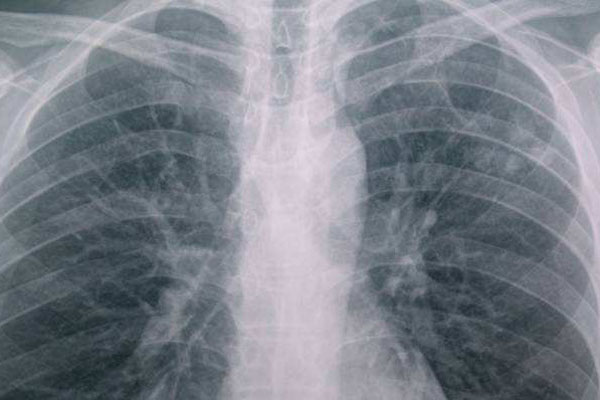

5、胸部透视

胸部透视也就是我们常说的X光检查,这个是检查肺部健康,肺部上的问题一下就明了。